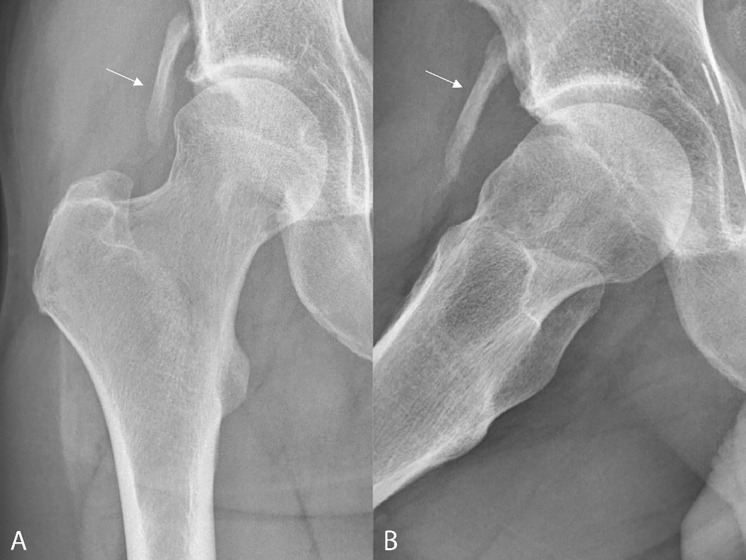

教学要点:正确诊断股直肌间接头异位骨化的线索是其位于髋臼边缘上方及其(倒置的)逗号状形态。

Teaching point: The clues to the correct diagnosis of heterotopic ossification of the indirect head of the rectus femoris are its location above the acetabular rim and its (inverted) comma‑like morphology.